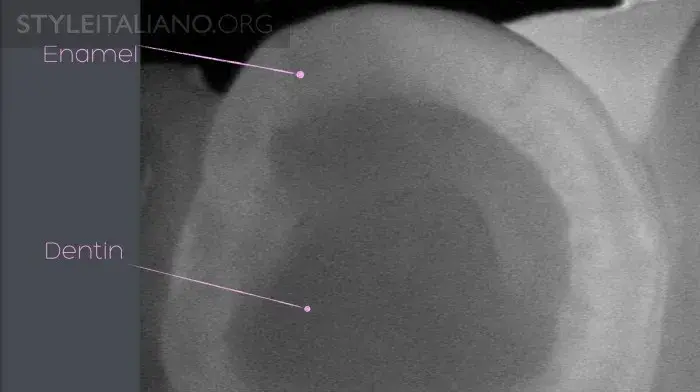

Рис. 3 Устройство Diagnocam, в основе которого лазерно-индуцированное просвечивание, позволяет нам просветить жевательные поверхности зубов. Выражается в серой шкале. Различные ткани зуба реагируют на свет по-разному: эмаль светлая, дентин более серый, а полости гораздо темнее.

Рис. 7 – Необходимо объяснить пациенту, где эмалево-дентинная граница и в каком случае поражение необратимо.